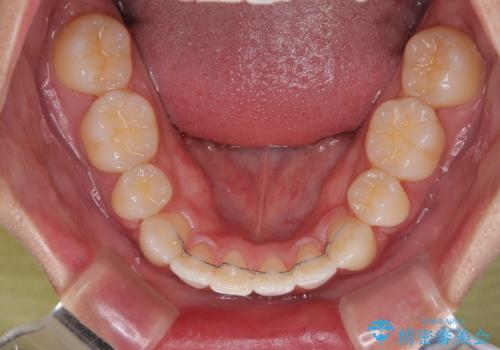

患者様の望んでいた通りの歯列や口元に仕上げることができました。

- 八重歯と口元の閉じにくさを気にして来院された患者様です。

非抜歯矯正で歯列を整えると、治療後に口元が今よりも突出する可能性が高かったため、上下左右の第一小臼歯4本を抜歯し、ワイヤー装置にて矯正治療を行うこととしました。